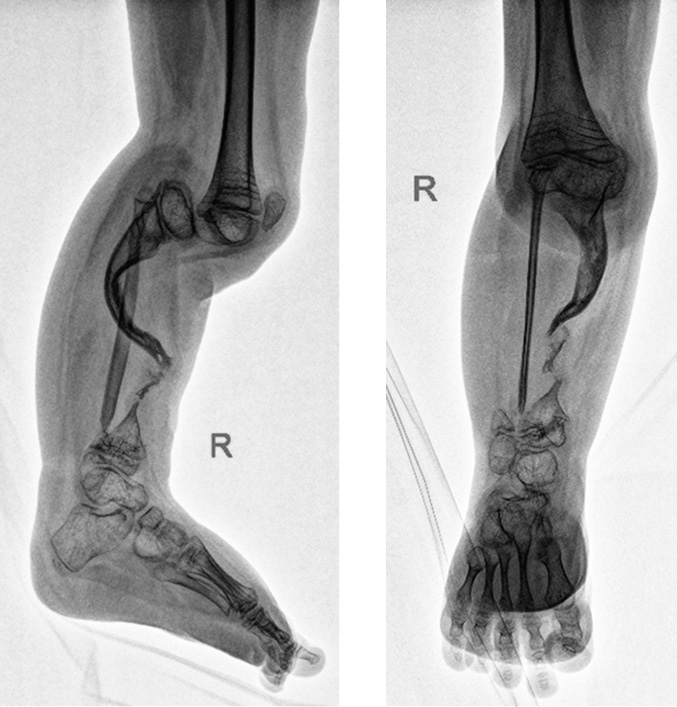

Fig. 5. Intraoperative radiographs of the right tibia bones in two views after microsurgical transplantation

Because of the fact that the patient was a citizen of another state and had difficulty in providing radiographs, the fixation period was almost 12 months. Before dismantling, in order to restore the range of motion in the right knee joint and due to long-term fixation in the CDA, a course of rehabilitation treatment was performed, including individual classes with an instructor of physical therapy and classes on the ARTROMOT device. When the EFD was unblocked at the level of the knee joint, movements in this joint were rocking (0°/0°/5°). Upon reaching passive flexion in the right knee joint up to 70° (0°/0°/70°), indications for dismantling were established. After removal of the EFD, at an X-ray examination, the leg-length difference was 8.3 cm (Fig. 6).